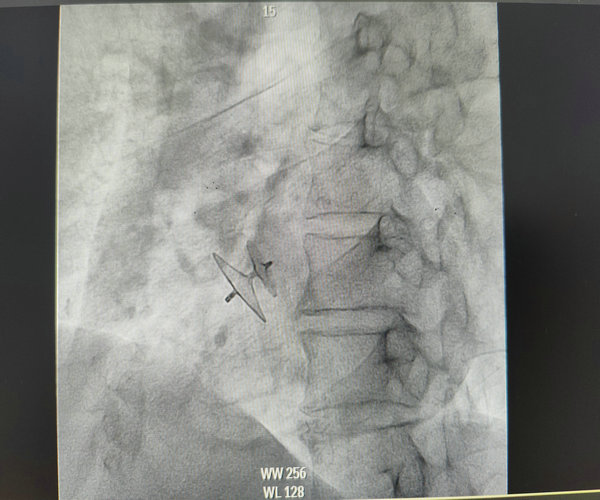

PFO封堵器释放成功

在李春峰主任的指导下,以及超声科等多学科的协助下,吴大鹏主治医师为马先生行卵圆孔未闭(PFO)封堵术。术中经患者右心房将导丝、导管送入左心房,在加硬导丝的支撑下送入输送鞘,通过输送鞘送入封堵器至卵圆孔未闭处,经超声提示封堵器位置良好,推拉实验封堵器稳固,超声心动图未见明显残余分流,遂完全释放封堵器,手术过程十分顺利,术后患者没有任何不适症状,对治疗效果非常满意。